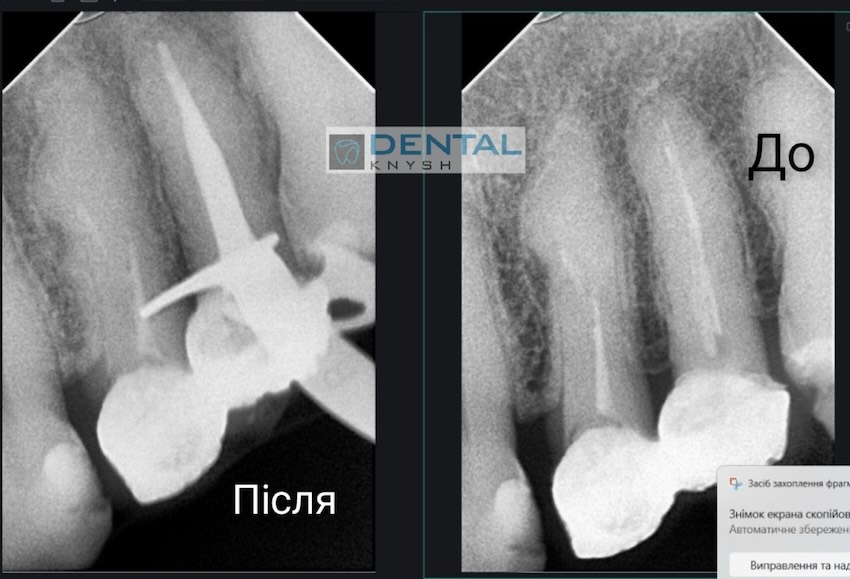

Лікар-ендодонтист Вадим Петриченко спеціалізується на лікуванні зубних каналів під мікроскопом.

Фото звіти

Більше фото звітів можна подивитися на сторінці Лікування зубів під мікроскопом